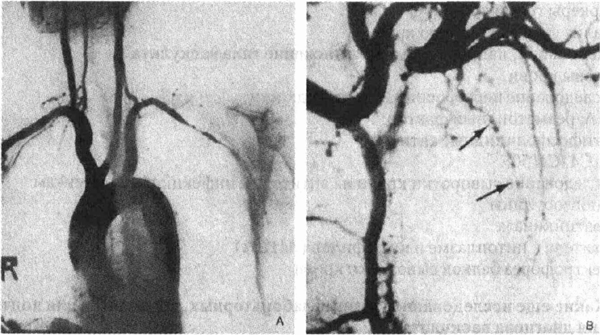

ангиографических признака васкулита.

Неравномерное снижение кровотока

Аневризмы (симптом "четок")

(См. рисунок на следующей

Ангиограммы больных, страдающих васкулитами.

А. Неравномерное снижение кровотока '/ и сужение просвета левой подключичной

артерии при болезни Такаясу. В. Классический симптом "четок": множественные

аневризмы сосудов у больного, страдающего изолированным васкулитом ЦНС